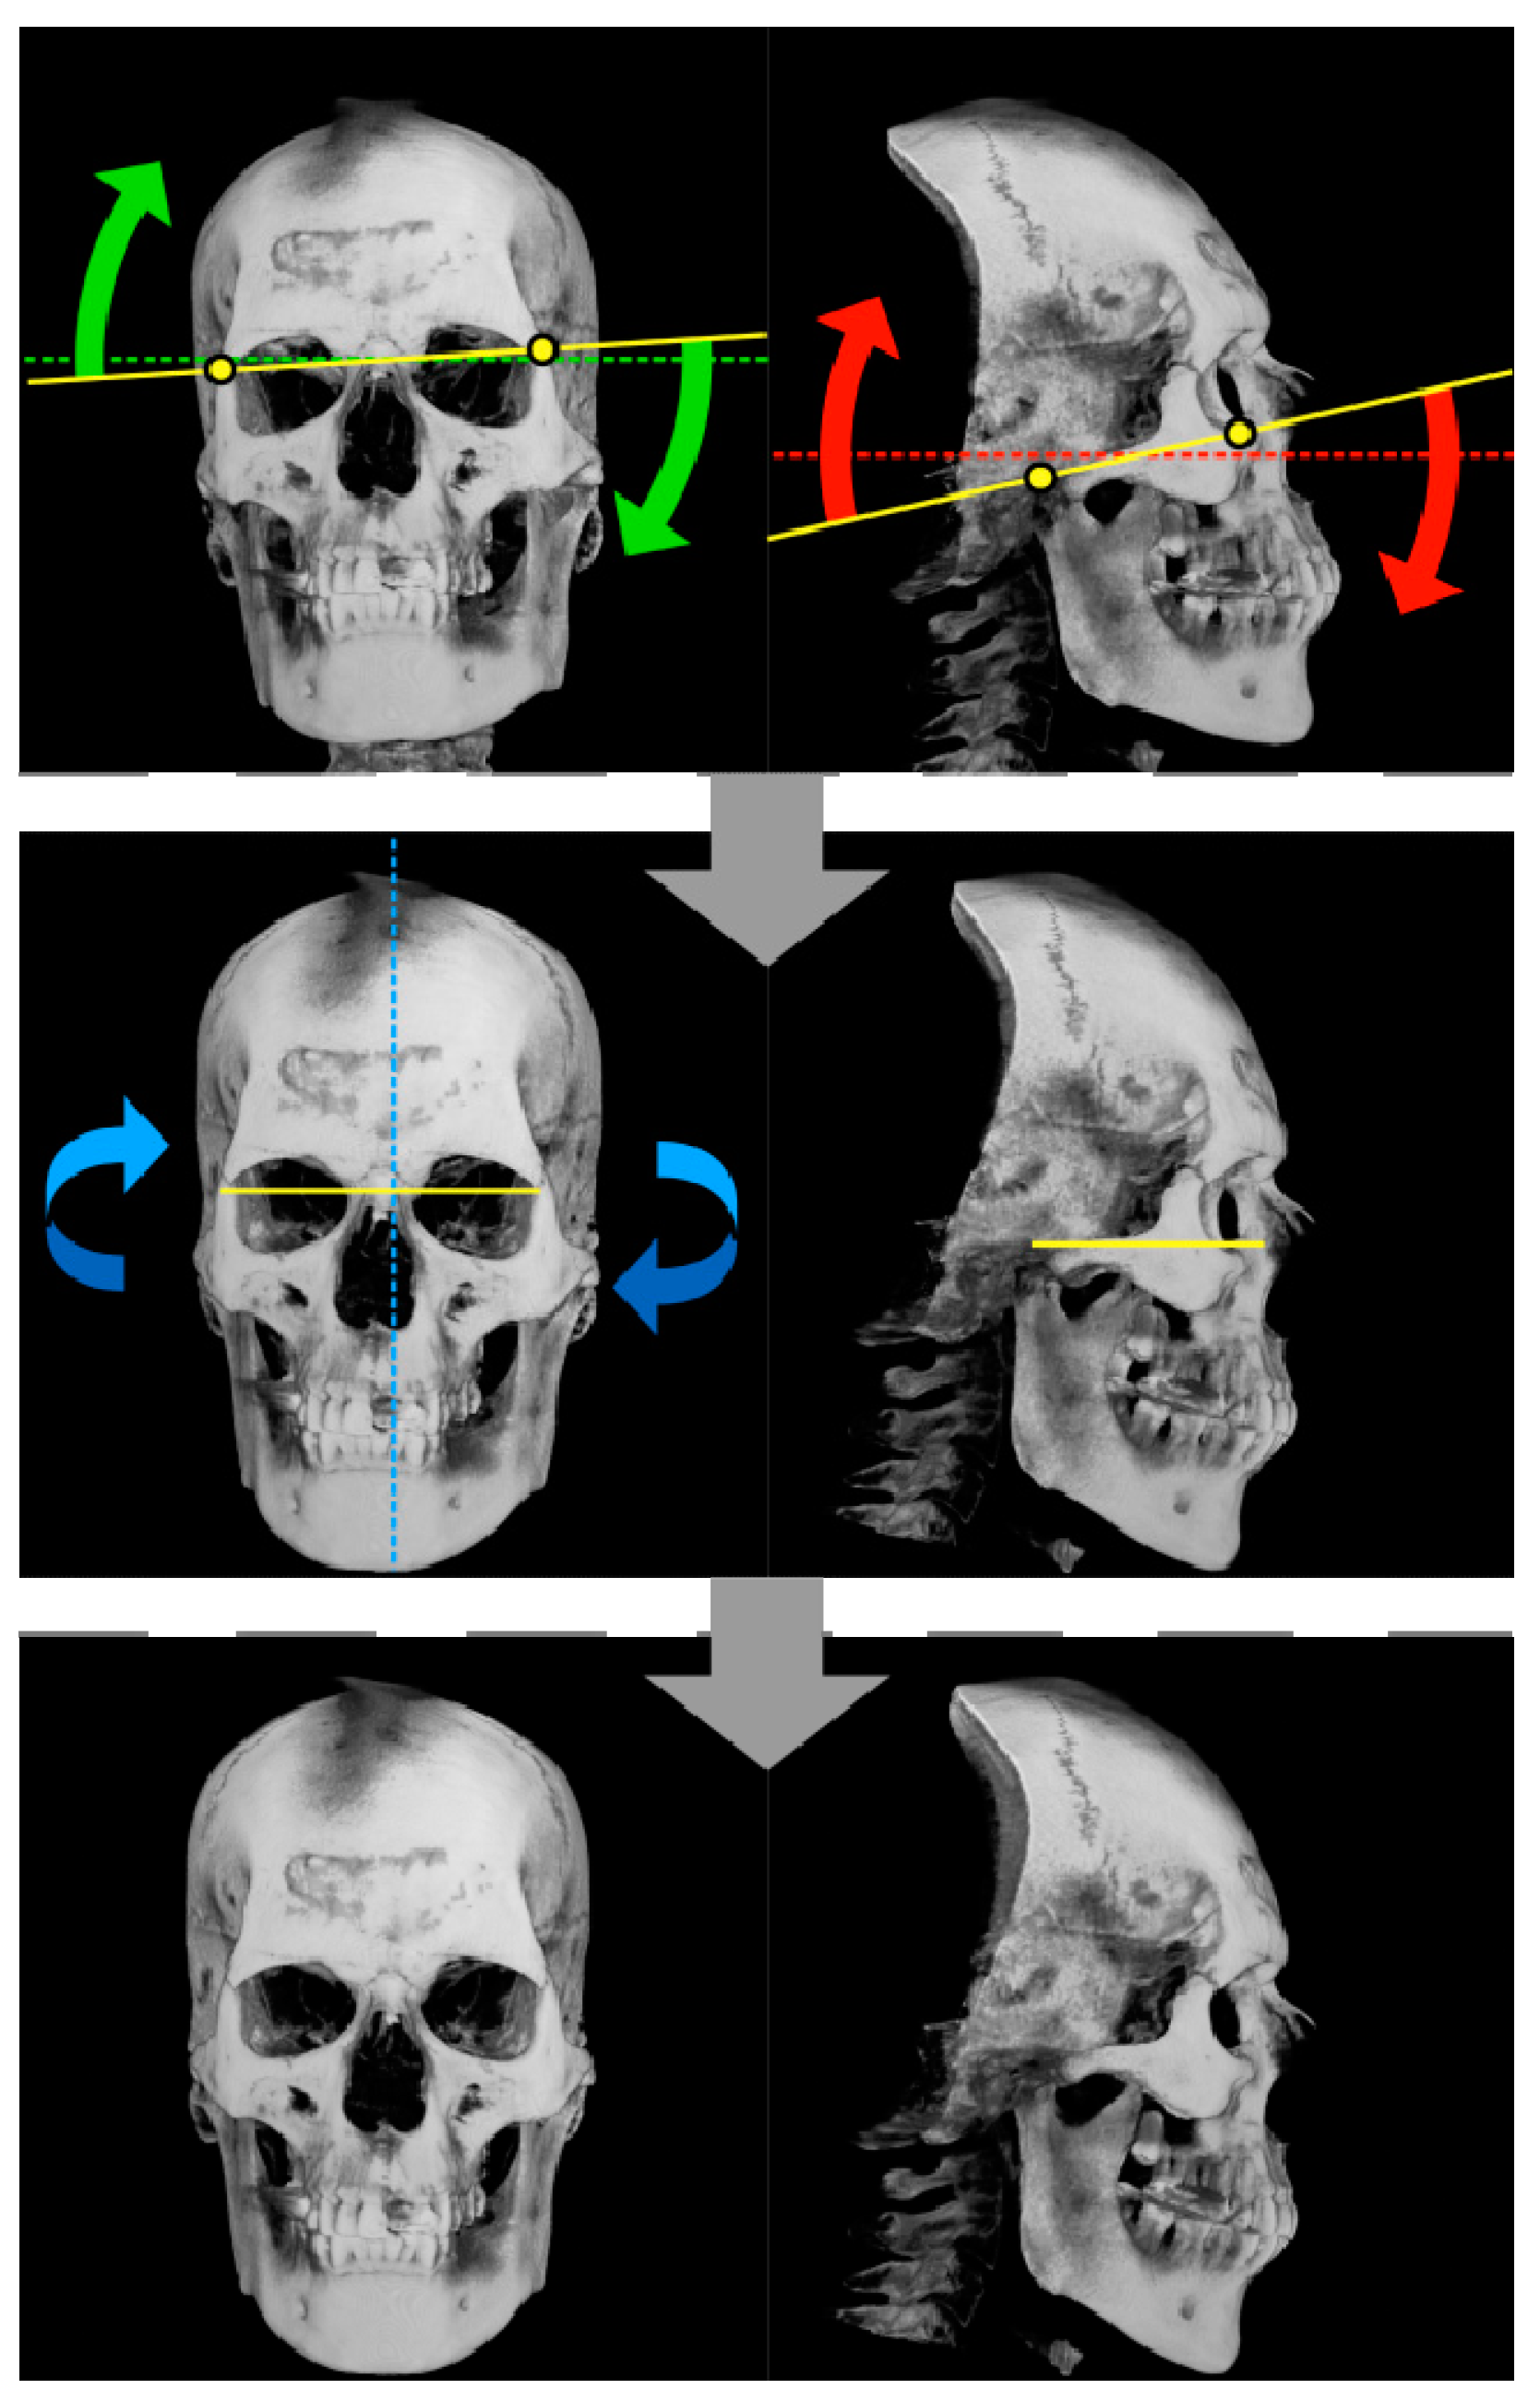

The craniofacial imaging data provided by doctors were not all straightforward. If the posture was inclined, the distances between the landmarks on the images would be compressed in the depth direction, which might result in inaccurate measurements. To prevent such compression, it was necessary to define the four landmarks for fixing the horizontal standard, to measure the two tilts of the axis, and to correct the inclinations of the imaging data before the actual measurements (Figure 4).

For example, it is assumed that the facial tilt of patients is characterized by front- and exact-side orientations of 0° and 90°, respectively. It is also assumed that the line connecting the left and right outermost edges of the orbits is horizontal and that its length is at its maximum when the patient is facing the front and at its minimum when the patient is facing exactly to the left side (Figure 5). If, instead, the patient is facing 8° to the left or right from the front, the measurement would be approximately 99.02% of the actual length (Figure 5 and Figure 6). In this case, if the actual length is 100 mm, the measurement would be 1 mm shorter. The error in the measurement increases rapidly as the inclinations increase.

The inclination of the horizontal tilt of the cranium was calculated from the positions of these four landmarks. By calculating back from that inclination, the inclination of roll and pitch rotation was corrected, and the horizontal orientations of the screen space and the cranium were matched. Regarding the yaw rotation, only the points that were inconsistent with the appearance of the rendered image were corrected. In this way, it was possible to easily identify the landmarks and obtain measurement images in which all the patients were shown in the ideal posture for measurement.

Figure 7. Progress of tilt correction. The left column is an anterior image, and the right column is a lateral image. The upper row is the correction of the inclination with respect to the horizontal plane. The points represent the landmarks used for correction, the broken lines are the reference plane, and the solid lines are the slopes with respect to the reference plane. The result of the tilt correction is shown by the solid line in the middle row. The middle row corrects the deviation in the front direction. The dashed line represents the axis of rotation. The lower row shows the state where all tilt corrections have been completed.